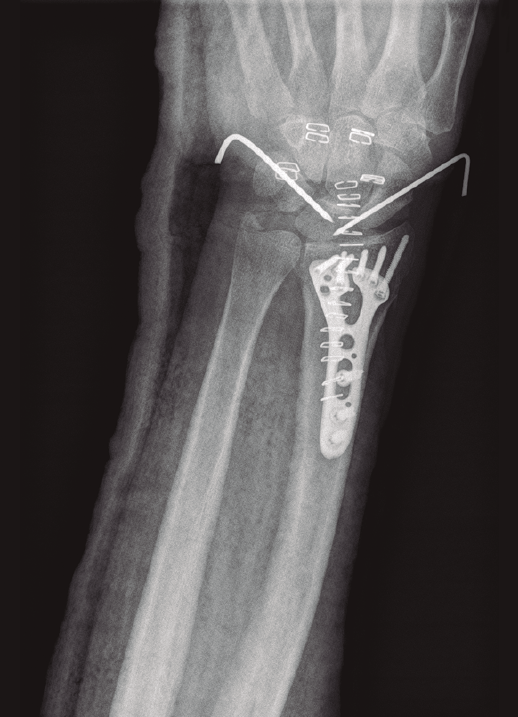

- Artroscopia de muñeca: afectación de la superficie articular, basándonos en los hallazgos observados en el estudio radiológico simple. La presencia de signos sugestivos de lesión ligamentosa en los estudios radiológicos prequirúrgicos constituye un aspecto importante a considerar para asociar una técnica artroscópica al tratamiento quirúrgico convencional. Estos signos radiológicos son: aumento del espacio escafolunar e inclinación dorsal del semilunar en el caso del ligamento interóseo escafosemilunar (Figura 1), la alteración de los arcos de Gilula con solapamiento lunopiramidal para las lesiones del ligamento interóseo lunopiramidal o la presencia de diástasis radiocubital y/o fractura de la apófisis estiloides cubital en lesiones del complejo del fibrocartílago triangular(8,10,20,21). Esto incluye las fracturas que afectan a la apófisis estiloides radial, ya que este patrón de fractura se asocia con frecuencia a lesiones del ligamento interóseo escafolunar(15,17).

Figura 1. Proyección lateral de muñeca con inclinación dorsal del hueso semilunar sugestiva de posible lesión del ligamento interóseo escafosemilunar.